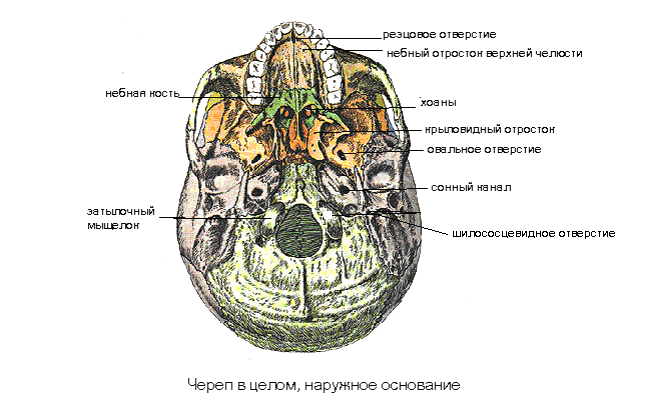

Анатомические детали: Фотографии топографии черепа с нижнего вида